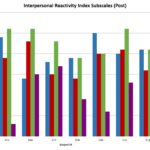

An Analysis on the Impact of Peer-Mediated Theatre Interventions for Children with Autism on Typically Developing Peers

The analysis of changes in model peers during behavioral interventions designed for children with Autism Spectrum Disorder.

Posted by Greta Clinton-Selin on Monday, June 5th, 2017 in May 2017, Behavioral Intervention, Peer-Study, Salivary Cortisol